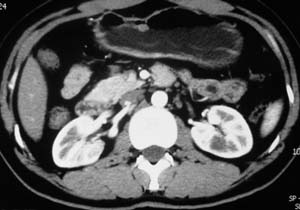

以下是引用子期在2010-3-19 20:47:00的发言:[br]血管畸形的ct增强应该有明显强化,本例并不相符合。本例双肾局部的略低密度影,累及肾盂,局部皮质明显变薄、内陷,增强扫描有轻度的强化,应考虑为炎性病变,患者为年轻男性,累及双肾的感染以结核较常见,可以没有明显的临床症状,尿中有时候也并不能查出什么;肾脓肿常有明显感染中毒症状,本例不符,另外一般的肾盂肾炎或肾小球肾炎通过小便就可确诊,其它还不能排除的是黄色肉芽肿性肾盂肾炎,然而单凭ct一般也很难鉴别。